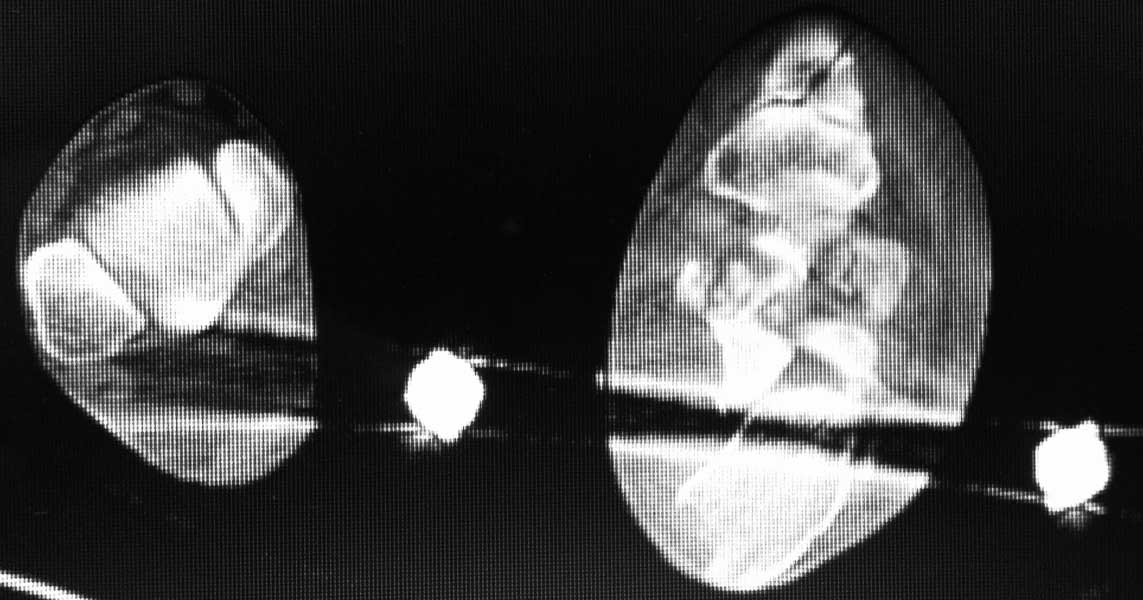

немного КТ

Даже на данном снимке можно . понять что перелом оскольчатый, внутрисуставной и захватывает заднюю и переднюю фасеты по крайней мере. Я тоже начал бы растягивать на аппарате (спицы спереди и сзади), но добавил бы locking plate открыто если больной кооперирующий и не курит. КТ нужна. Goodluck . Аарон

На аппарате к сожалению не возможно провести репазицию отломков при оскольчатых переломах пятки. Единственное что вы добетесь это востановите свод стопы. Так как поциент молодой я всётаки склонен к открытому методу используя специальную пластину. Во время операции будте внимательны к мягким тканям.